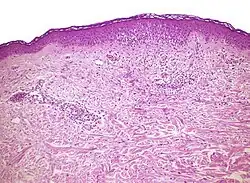

Interface dermatitis

These are sorted into either:[2]

- Interface dermatitis with vacuolar change

- Interface dermatitis with lichenoid inflammation

Interface dermatitis with vacuolar change

| Main conditions[6] | Characteristics | Micrograph | Photograph | |

|---|---|---|---|---|

| Generally/Not otherwise specified | Typical findings, called "vacuolar interface dermatitis":[6]

|

![]() |

||

An interface dermatitis with vacuolar alteration, not otherwise specified, may be caused by viral exanthems, phototoxic dermatitis, acute radiation dermatitis, erythema dyschromicum perstans, lupus erythematosus and dermatomyositis.[2]